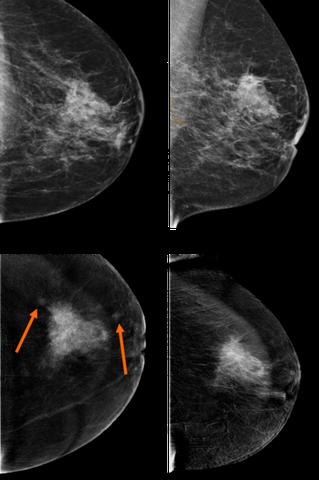

Dreidimensionale Mammographie (DBT)

Wenn der Befund der zweidimensionalen Mammographie unklar ist oder eine Stelle nicht gut diagnostizierbar ist, kann ein modernes dreidimensionales Mammographieverfahren namens digitale Brust-Tomosynthese (DBT) eingesetzt werden. Bei diesem Verfahren werden mehrere Schichten der Brust aufgenommen, um ein dreidimensionales Bild zu erzeugen. Die DBT ist sensitiver als die herkömmliche 2D-Mammographie, führt jedoch auch zu mehr falsch positiven Befunden.

Dreidimensionales Mammographie-Verfahren

Wenn der Befund der zweidimensionalen Mammographie unklar ist oder eine Stelle nicht gut diagnostizierbar ist, kann ein modernes dreidimensionales Mammographie-Verfahren verwendet werden – die digitale Brust-Tomosynthese (DBT). Dabei werden mehrere Schichten der Brust aufgenommen, um ein dreidimensionales Bild zu erzeugen. Die DBT ist sensitiver als die herkömmliche 2D-Mammographie, hat aber auch mehr falsch positive Befunde zur Folge.

Wenn der Befund einer zweidimensionalen Mammographie unklar ist oder eine Stelle nicht gut diagnostizierbar ist, kann ein modernes dreidimensionales Mammographieverfahren namens digitale Brust-Tomosynthese (DBT) verwendet werden. Dabei werden mehrere Schichten der Brust aufgenommen, um ein dreidimensionales Bild zu erzeugen. Die DBT ist sensitiver als die herkömmliche 2D-Mammographie, hat aber auch häufiger falsch positive Befunde zur Folge.